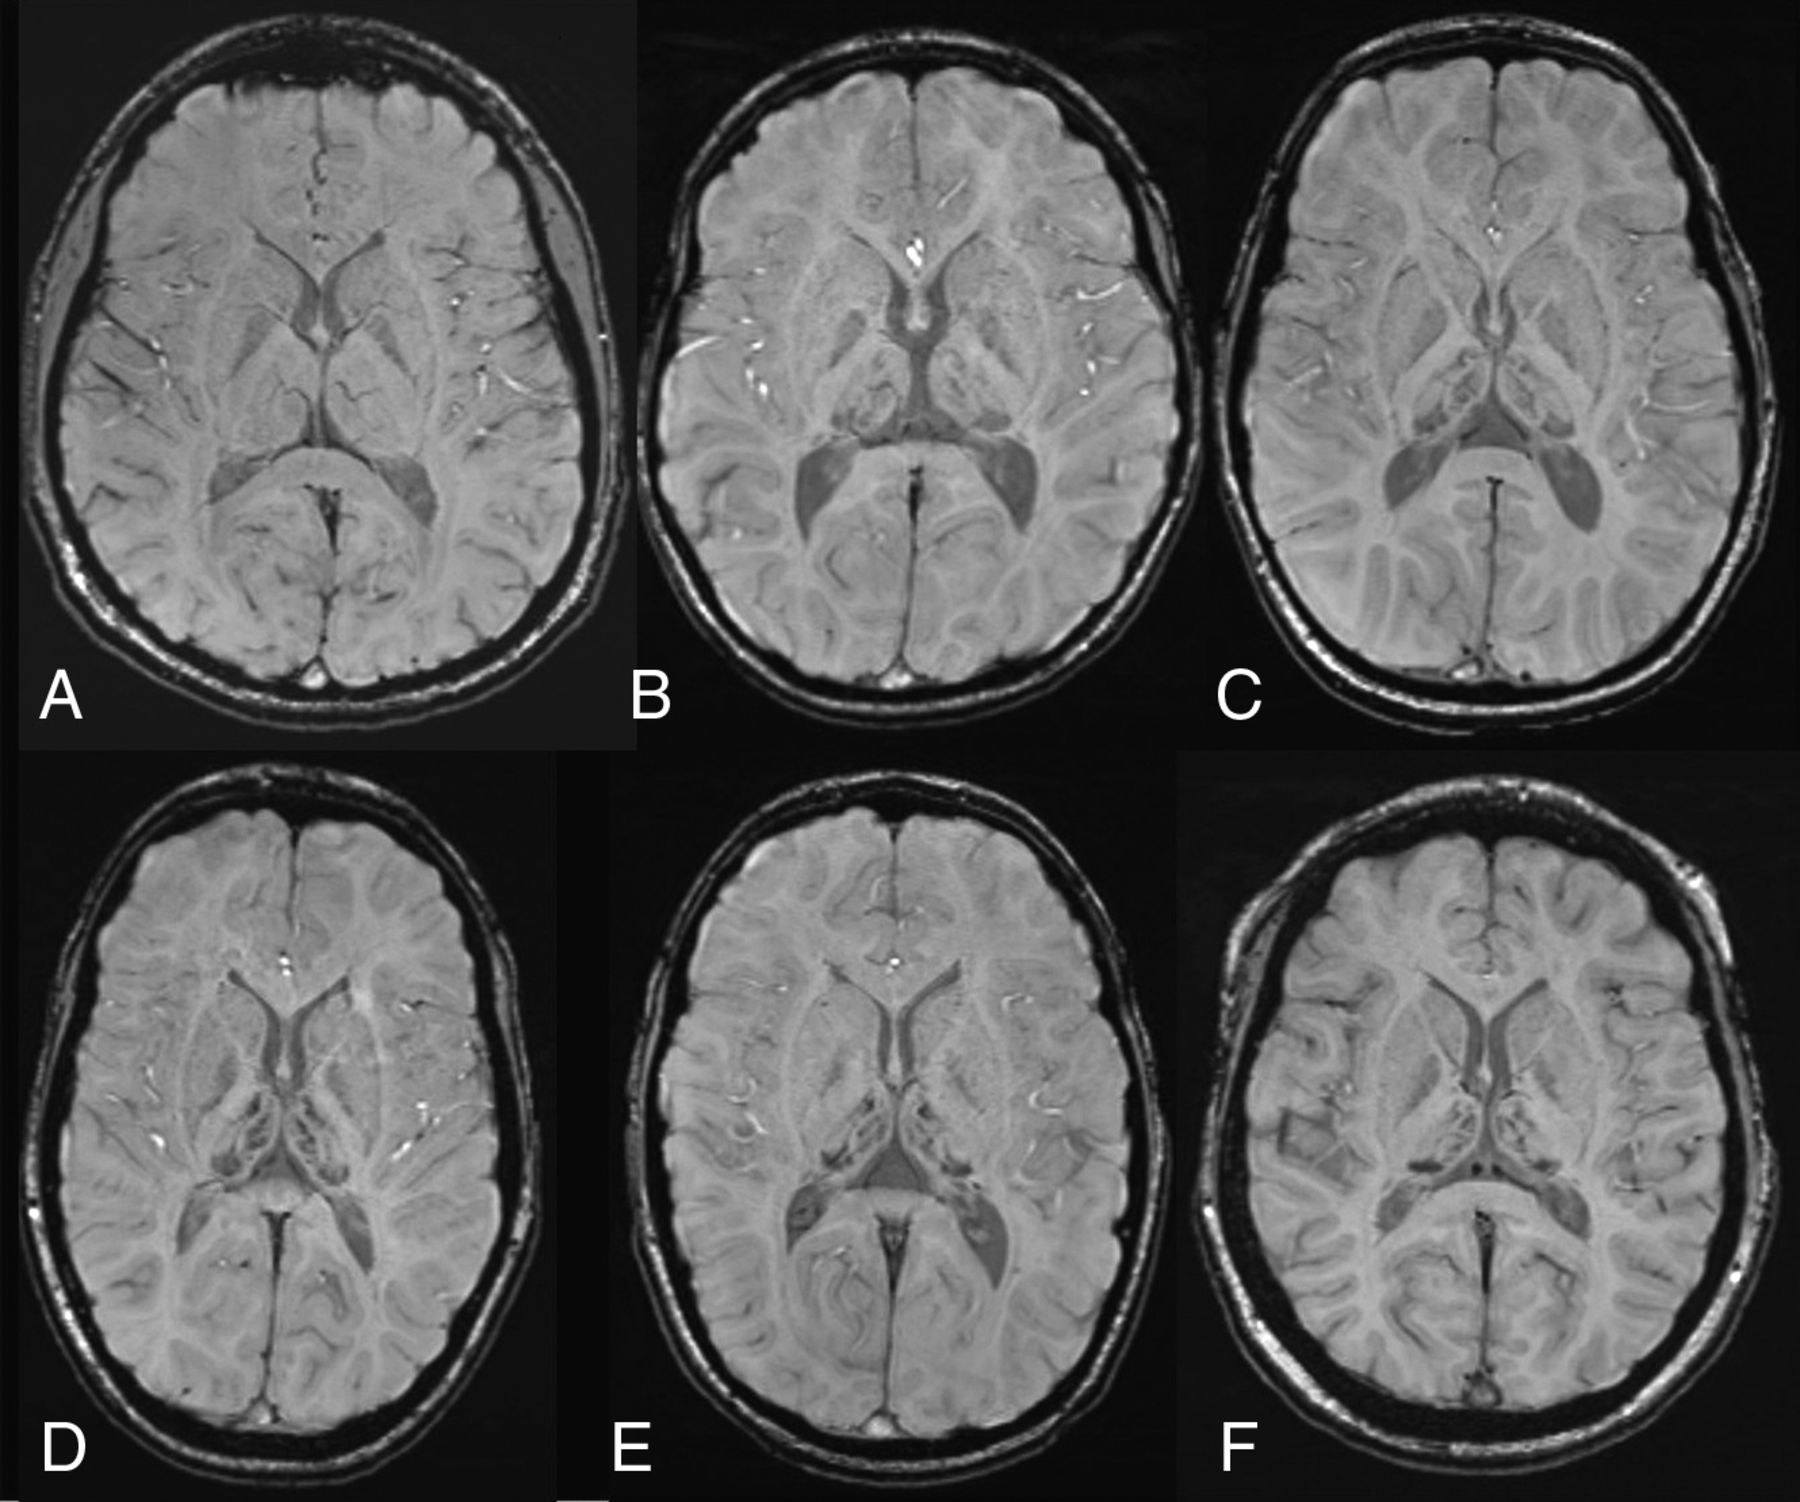

Susceptibility-weighted axial images at the level of basal ganglia and thalami. A, A healthy control, an 11-year-old girl with normal findings. B–F, Five patients with AGU at different ages (7.9, 9.5, 11.4, 13.8, and 14.2 years) show a strikingly similar distribution of hypointensity in deep gray matter structures, with a maximum-intensity decrease in the pulvinar nuclei. Patchy decrease is also noted in the medial and anterior thalamic nuclei. Some signal intensity decrease is also seen in the globi pallidi.

Interestingly, all 13 patients with good-quality SWI showed a highly similar distribution of hypointensity in the thalamic nuclei (Fig 1). The most evident hypointensity was found in the pulvinar nuclei. Patchy hypointensities were also found, especially in the medial and anterior nuclei. Moreover, some hypointensity was noted in the globi pallidi in 6 of the patients, especially in the medial aspect. In 5 patients between 11.5 and 15.0 years of age, hypointensity was also evident in the substantia nigra. The filtered-phase images indicated accumulation of paramagnetic compounds in these areas (Fig 2). No microhemorrhages, lobar hemorrhages, or signs of subarachnoid hemorrhage were seen.